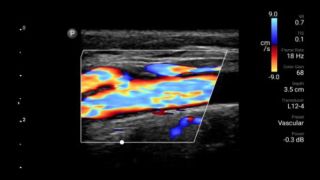

Echografieonderzoeken kunnen helpen om huidabcessen te identificeren en succesvol te behandelen.

Lumify kan helpen de subtiele details van een beeld zichtbaar te maken en afwijkende weefselstructuren bloot te leggen vanuit verschillende hoeken. Hierdoor kunt u met vertrouwen realtime beslissingen nemen, van diagnose tot herstel.

POC-echografie voor zacht weefsel